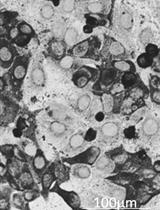

Here, we describe in detail a novel IFC protocol that allows specific detection and quantification of citrullination of histone 4 (H4cit3) as a NETs marker in whole neutrophils, prior to the release of the DNA and the cytoplasmic protein strands into the extracellular space. Other analysis parameters that look at nuclear and cellular morphological changes (nuclear decondensation and supercondensation, multi-lobulated nuclei and cell membrane damage) can bring additional information on the behavior of the analyzed neutrophil population. To establish our methodology we determined the responses of healthy human neutrophils treated for 5 different periods of time (between 2 min and 60 min) with NETs agonists: pharmacological inducers, PMA and calcium ionophore (a well-known inducer of histone citrullination, and for our experimental conditions, the positive control), Hemin (an inducer present under hemolytic conditions) and LPS and IL-8 (inducers associated with infectious pathogens). We used in vitro fluorescence microscopy to confirm the formation of DNA-elastase-MPO strands in healthy neutrophils treated with the stimuli used for the IFC tests (Barbu et al., 2020). We further validated this technique in untreated and Hemin-treated neutrophils from healthy donors and patients with sickle cell disease at steady state (Barbu et al., 2019).

Figure 1. Day-by-day description of the major steps for specific detection of NETosis markers by Imaging Flow Cytometry. A. One-step polymorphoponuclear (PMN) cells isolation from whole blood with Polymorphprep medium; with this method neutrophils purity should be consistently above 80%. Total processing time: 90 min. B. An example of correct separation of whole blood by using Polymorphprep gradient medium. C. Detailed description of polymorphonuclear cells treatment and staining procedure. A time recommendation is not included for the neutrophil stimulation step as researchers should choose an appropriate treatment time according to their experimental purpose. Each washing step might need up to 20 min to complete, depending on the number of samples processed. This time should be taken into account while calculating total time required to complete all steps per day. Short final wash followed by samples storage at 4 °C. Total stimulation and staining processing time for Day 1: 4+ h.